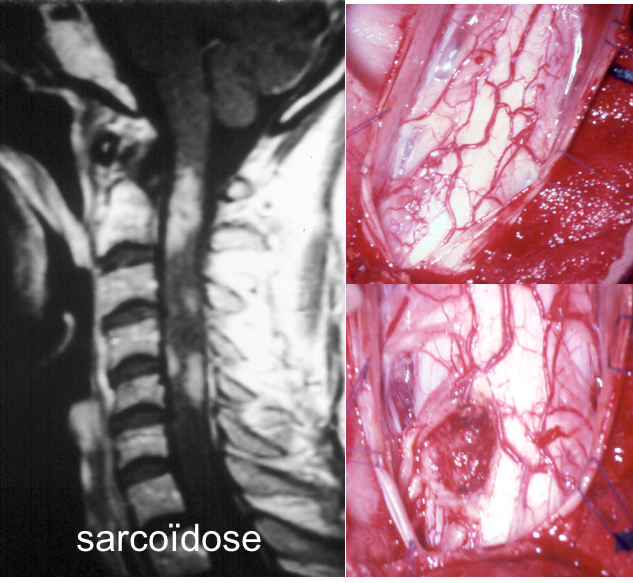

la sarcoïdose

le contraste entre une lésion infiltrante, qui ressemble à un gliome de haut grade, et la faible évolutivité clinique peut indiquer une pseudo-tumeur liée à la sarcoïdose (ci-contre).